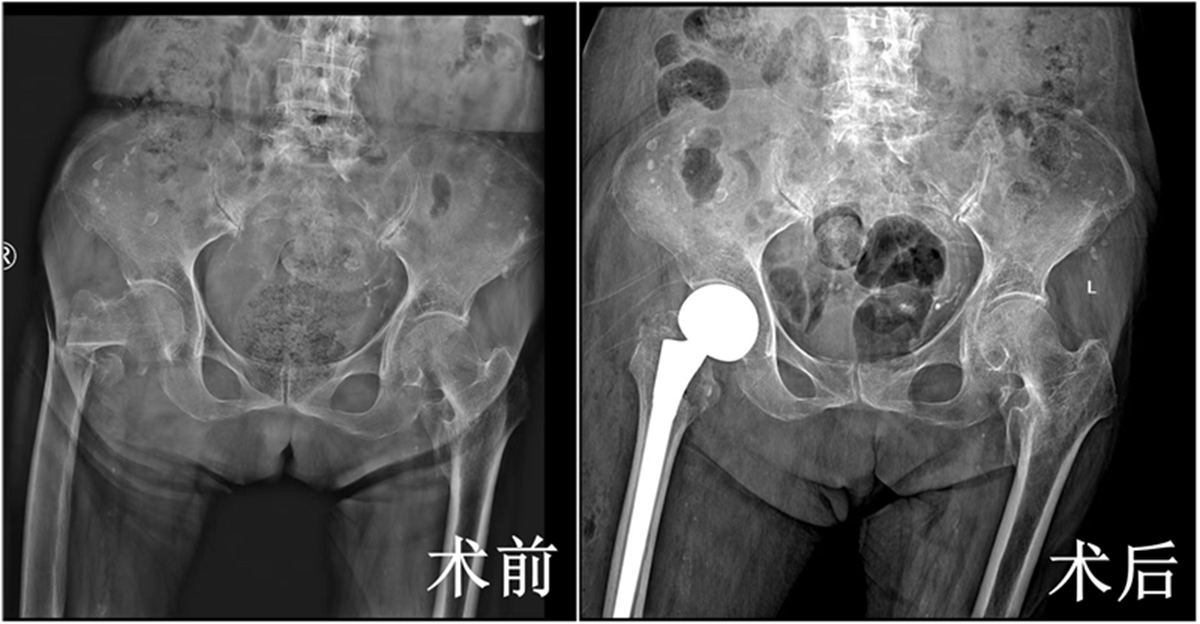

华商网讯(记者 袁毛毛) 近日,一位101岁高龄的股骨粗隆间骨折患者在西安市红会医院关节病院综合病区、心内科、麻醉科等多学科团队(MDT) 的精密协作下,成功接受了直接前方入路(DAA)微创半髋关节置换术。

术前,心内科团队通过心脏超声、冠脉CTA评估心功能,利用药物对患者的心功能进行了优化调整,将血压、心率等指标控制在手术最佳窗口期为手术规划安全航道;术中,麻醉科团队采用椎管内麻醉+轻度镇静方案,既确保手术无痛,又减少了对患者心肺功能和大脑意识的抑制,实时监测数据波动,动态调整用药维持生命体征平稳。骨科团队则采用直接前方入路(DAA)微创技术,经神经肌肉间隙入路,实现7cm小切口、30分钟短时、80ml低出血;术后患者无体位限制,次日即辅助下站立行走,预计将于近日完成康复评估后顺利出院,创高龄患者快速康复范例。